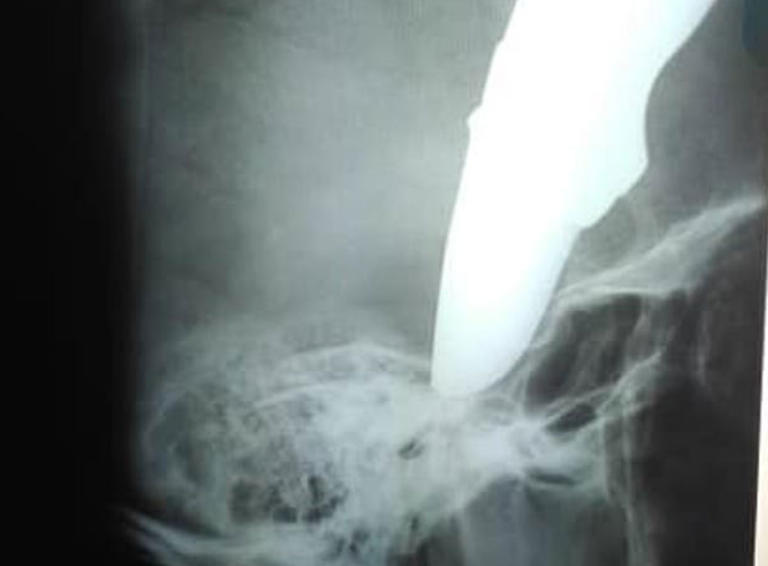

Ο Σον Γουέιν πήγαινε στην δουλειά του με το ποδήλατό του. Ξαφνικά, δέχθηκε επίθεση από δυο αγνώστους για να του κλέψουν το ποδήλατο. Εκείνος αντιστάθηκε και τότε, ο ένας του κάρφωσε ένα μαχαίρι στο κεφάλι! Ο 34χρονος δεν τα έχασε και αφού κατάφερε να τους ξεφύγει συνέχισε για 800 μέτρα με το ποδήλατο μέχρι να φτάσει στον γιατρό προκειμένου να σώσει την ζωή του με το μαχαίρι των 15 εκατοστών καρφωμένο στο κεφάλι του!

Όλα έγιναν στην πόλη Στραντ κοντά στο Κέιπ Τάουν στη Νότια Αφρική στις 19 Νοεμβρίου. Ο 34χρονος μόλις έφτασε στο νοσοκομείο με απίστευτη ψυχραιμία είπε: «Μήπως μπορεί να με δει ένας γιατρός;» Αμέσως σήμανε συναγερμός! Ο Σον Γουέιν μπήκε στο χειρουργείο και η κατάστασή του σύμφωνα με τους γιατρούς είναι σταθερή. Όπως είπε ένας από τους γιατρούς, ο 34χρονος ήταν πολυ τυχερός παρότι το μαχαίρι είχε καρφωθεί πολύ βαθιά στο κρανίο του.

Οι φωτογραφίες του Γουέιν έκαναν τον γύρο του διαδικτύου και είναι πραγματικά σοκαριστικές. Όπως εντυπωσιακό είναι και το πόσο ψύχραιμος δείχνει.